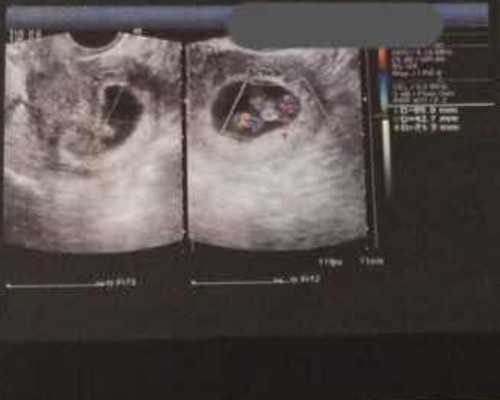

但是在实验室的试管里形成胚胎之后,还会再转移到女性的子宫里面,在子宫里健康成长,和其他宝宝是一样的。

2、在从母亲身体里取卵的时候,是取得多个卵子进行结合,而且为了提高成功率,是将多个结合成功的胚胎移植到子宫进行受孕,所以生双胞胎的几率比自然生双胞胎的几率高点儿,不过怀孕期间风险性也是比较大的。